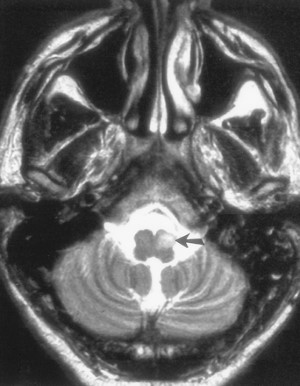

Mối liên hệ cụ thể giữa tổn thương nguyên phát (chủ nếu là nhồi máu, xuất huyết, hoặc thoái hoá) và sự tiến triển thoái hoá nhân trám theo một trong ba dạng mô tả dưới đây và dễ hiểu hơn nhờ sơ đồ minh hoạ trên. Khi tổn thương nguyên phát khu trú ở dải trung tâm trần cầu não thì phì đại nhân trám cùng bên (Hình 10), bởi vì chỉ có các sợi cùng bên bị tác động. Khi tổn thương nguyên phát ở nhân răng hoặc ở cuống tiểu não trên thì thoái hoá nhân trám đối bên. Khi tổn thương liên quan đến cả hai dải trung tâm trần cầu não và cuống tiểu não trên thì thoái hoá nhân trám cả hai bên.

Hình10a. Bệnh nhân 36 tuổi có tiền sử tăng huyết áp và đột quỵ trước đây, vào viện vì xuất hiện rung giật theo nhịp chi trên bên phải. Ảnh T2W fast spin-echo (TR = 6500; TE = 119; number of signals = 2) não trong giai đoạn có triệu chứng ở vùng nối cầu não và trung não. Có dải giảm tín hiệu rõ bên trong vùng teo khu trú phần sau trần cầu não bên trái (mũi tên), đây là khe phủ hemosiderin và ferritin sau chảy máu cũ. Vị trí nàu bao gồm dải trung tâm trần cầu não (vòng tròn rắng) bên trái. (December 1999 Radiology, 213, 814-817)

Hình 10b. Ảnh T2W ở phần tuỷ thấp hơn cho thấy cường độ tín hiệu cao và to không cân xứng phần trước tủ bên trái tương ứng với vùng thoái hoá phì đại nhân trám dưới bên trái (mũi tên). (December 1999 Radiology, 213, 814-817)